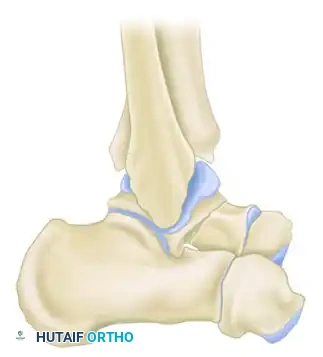

Surgical Anatomy and Biomechanics

Any fracture that involves a joint presents a difficult reconstructive problem, and this is especially true of a primary weight-bearing joint like the ankle and subtalar complex. Approximately 60% to 70% of the surface of the talus is covered by articular cartilage, leaving a limited footprint for vascular penetration. For this reason, almost any fracture of the talus involves a joint surface and threatens the blood supply.

More weight per unit of area is borne by the superior articular surface of the talar dome than by any other bone in the human body. Accurate reduction is therefore essential to reestablish the precise position of its articular surfaces. Any residual irregularity of the joint surfaces will inevitably produce rapid posttraumatic arthritic changes upon the resumption of motion and weight-bearing.

Clinical Pearl: The blood supply to the talus is retrograde. The artery of the tarsal canal (a branch of the posterior tibial artery) supplies the majority of the talar body. The deltoid branch provides a critical, often sole remaining blood supply in displaced fractures. Surgical approaches must meticulously preserve the deltoid ligament to avoid iatrogenic devascularization.